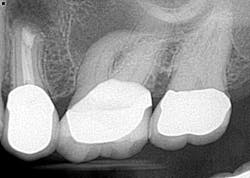

Case report A healthy 61-year-old female presents with a chief complaint of pain and discomfort in the upper left quadrant. A radiograph revealed a large radiolucency at the apex of tooth No. 12. An irregular root apex was also noted. Clinically No. 12 was sensitive to percussion and palpation in the buccal vestibular area. There was no response to cold. Diagnosis was necrotic tooth No. 12 with associated periapical abscess. RCT was recommended and the patient was referred to a specialist for completion. RCT was completed — no complications were noted and the prognosis was given as good. (Figs. 1 and 2) The patient was placed on recall by the endodontist for reevaluation of the lesion in 12 months.Fig 1. Fig. 2Eight months later, the patient presented back to the office stating that she felt pressure again in the upper left area. A radiograph of No. 12 showed an increased radiolucency around the apex of tooth No. 12. Furthermore, there was a draining fistula in the buccal vestibule. Diagnosis was persistent infection/disease, likely due to the initial presentation and presence of the cyst. (Fig. 3)